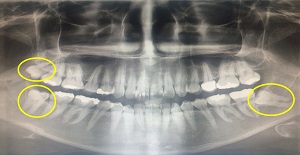

- 매복사랑니, 뿌리가 신경관과 가까운 경우 많아 주의 필요, 잘못 발치할 경우 감각 이상 증상 나타날 수도 - 개인에 따라 치아 발달 상태 다르기 때문에 정기검진 통해 꾸준히 관리해야 치아 건강 지킬 수 있어 직장인 박씨(33)는 스케일링을 받으러 치과를 찾았다가 오른쪽 아래에 사랑니가 있다는 사실을 알게 됐다. 가끔씩 잇몸 안쪽에 불편함을 느꼈지만 사랑니가 나오면서 생긴 통증이라 생각지도 못했던 것. X-ray 촬영 결과 위쪽에도 사랑니가 있었고, 왼쪽에는 매복된 사랑니까지 존재한다는 사실을 알게 돼 깜짝 놀랐다. 잇몸으로 덥혀 있었기 때문에 정작 본인은 사랑니를 갖고 있다고 생각지도 못했던 것이다. 사랑니는 대게 상하좌우에 각각 1개씩 나는데 4개 모두 정상적으로 나는 사람은 극히 드물다. 보통 성인의 경우 28개 치아 개수에 비해 턱이 작기 때문에 사랑니가 온전히 나오지 못하고 누워서 나거나 삐뚤게 되는 경우가 대부분. 특히 잇몸 안에 묻혀 보이지 않는 매복사랑니의 경우 육안으로 잘 보이지 않아 사랑니가 없다고 생각하다 통증이 생겨 치과를 방문해 알게 된다. 아프지도 않은데 꼭 뽑아야 할까 의문을 갖는 사람들도 많다. 사랑니라고 해서 무조건 발치가 필요한 것은 아니다. 다른 치아처럼 반듯하게 자라 청결상태를 잘 유지한다면 어금니처럼 저작기능을 할 수 있다. 하지만 삐뚤게 났거나, 잇몸 속에 숨어 있는 경우는 칫솔질이 제대로 되지 않아 관리가 힘들어 충치나, 잇몸 염증, 구취 등을 유발하게 된다. 이를 방치하면 사랑니 바로 앞 치아까지 충치가 생기거나 염증으로 인해 잇몸과 얼굴이 붓고 일상생활에 불편을 줄 수 있어 발치가 필요하다. 특히 매복사랑니는 주변 치아 옆 뿌리를 손상시키거나 잇몸을 아프게 할 수 있어 예방 발치를 하는 것이 좋다. 일산사과나무치과병원 구강외과에서 매복사랑니를 발치한 내원 환자 수를 조사한 결과를 보면 2013년 1,624명에서 2014년 1,710명, 2015년 1,793명으로 꾸준히 증가하고 있는 추세로 나타났다. 사랑니에 통증이 생겨 발치하는 경우 외에도 최근 스케일링 보험화로 치과 정기 검진을 받는 사람들이 늘어나면서 매복된 사랑니를 존재를 알게 돼 예방 발치하는 사람이 증가하고 있는 것으로 분석된다. 일산 사과나무치과병원 구강외과 김영연 병원장은 “사랑니 존재 여부는 X-ray 검사로 간단히 확인할 수 있는데 옆으로 누워난 사랑니의 경우 통증 없이 앞어금니까지 충치가 생기게 하는 경우가 많으므로 미리 검진을 받고 아프지 않아도 예방적으로 발치하는 것이 좋다”며 “특히 임산부의 경우 아무래도 임신 중에는 사랑니를 발치하기 어렵기 때문에 미리 검진을 통해 사랑니 상태를 확인할 수 있어야 한다”고 말했다. 사랑니가 난 상태에 따라 발치 방법은 다르다. 매복사랑니는 뿌리가 신경관과 가까운 경우가 많은데 이 신경관은 잇몸, 볼, 입술, 턱 주변의 감각을 담당하고 있어 손상 시 해당 부위에 감각 이상 증상이 나타날 수 있기 때문에 특히 주의해야 한다. 발치할 때 잇몸을 절개해 치아를 잘라서 몇 조각으로 나눠 발치 하는데, 매복사랑니 발치도 전문적인 수술에 해당하므로 CT 촬영을 통해 사랑니와 아래턱 신경 거리 및 위치를 정확히 확인하고 수술해야 한다. 김원장은 “아프지 않으면 치과를 찾지 않는 경우가 많은데 개인에 따라 치아 발달 상태는 다르기 때문에 20대에 사랑니가 나지 않았다고 해서 사랑니가 없다고 섣부르게 자가 진단하지 말고 정기 검진을 통해 정확한 상태를 확인해야 한다”며 “사랑니 발치 후 이틀 정도는 심한 운동이나 사우나 등은 삼가고, 구강에 압력을 줄 수 있는 빨대 사용이나 침 뱉기는 자제해야 한다. 발치 후 2~3일까지는 냉찜질을 해주는 것도 부기와 통증을 줄이는데 도움이 된다”고 덧붙였다. 【도움말 = 사과나무치과병원 구강외과 김영연 병원장】 [김현지 기자] munandpil@nate.com | |||||||||